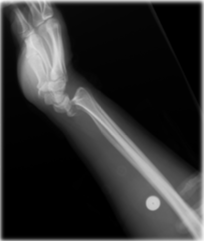

Tipo de fractura

Fractura de Barton (volar o anterior)

Mecanismo de lesion de esta fractura

Fractura de barton

Caída sobre la muñeca en dorsiflexión con el antebrazo en SUPINACIÓN

Tratamiento de esta fractura

Quirurgico, con placa